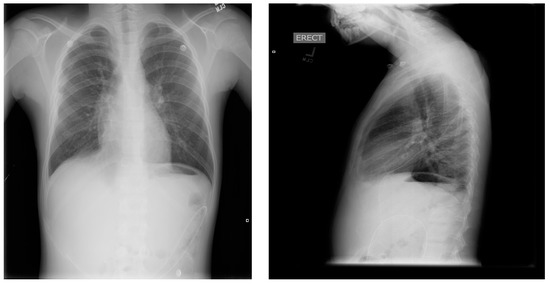

The pressure gradient necessary to open the valve is 3 cm of water, but this can be overcome by compressing the bulb which houses the one-way valve, forcing flow from chest to abdomen. This pressure gradient is noted on the packing insert for the shunt and is outlined within the instruction manual for the Denver shunt on the manufacturer, Beckton, Dickinson, and Company’s (Franklin Lakes, NJ, USA) website. The patient continued with monthly simple transfusions, and hydroxyurea was instituted. Following the PP shunt placement, he required one hospitalization for re-accumulated chylothorax and had a thoracostomy tube placed. Significant drainage was felt to be secondary to the obstruction of the PP catheter and to non-adherence regarding compressing the shunt reservoir bulb daily in order to prevent obstruction of its one-way valve. The PP catheter was cleared by pressure on the shunt bulb, which was continued at home a few times daily. Repeat imaging with Duplex ultrasound showed no change in the thrombus, consistent with fibrotic changes. The PP shunt was removed about 6 months after placement, and he has remained free of pleural effusion (Figure 7). The decision to remove the shunt was based on an asymptomatic period of about 6 months, parent comfort level, and the surgeon’s past experience with PP shunts. He has continued to be managed with hydroxyurea, with dose escalation to the maximally tolerated dose, and he has transitioned off transfusions.

Figure 7.

Most recent chest X-ray, several months after removal of shunt.